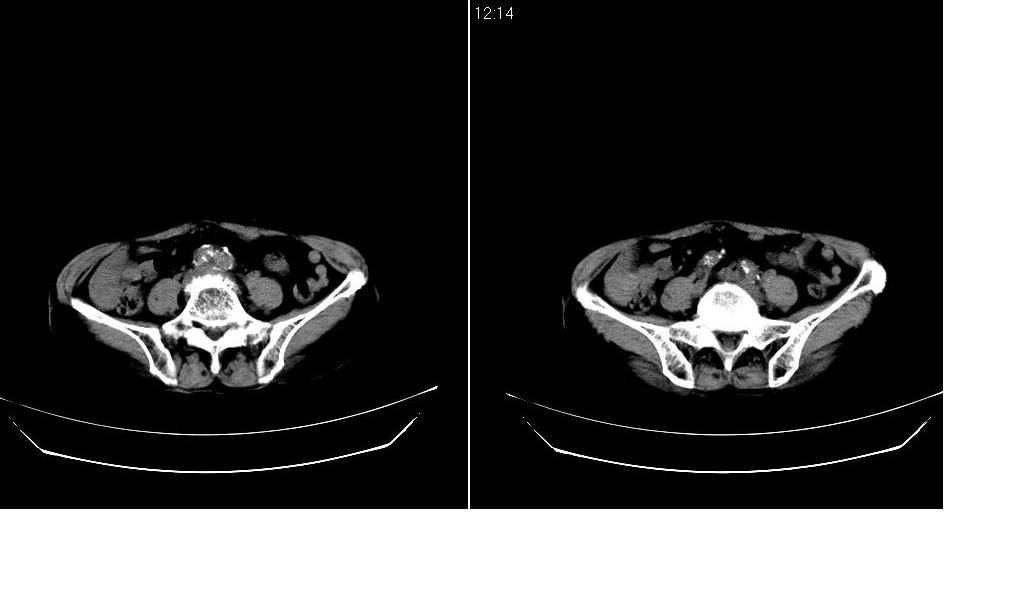

标题: CT12001:上腹部CT平扫

女73岁,病史不详,腹主动脉增宽.

考虑:腹主动脉瘤。建议增强。

考虑:腹主动脉瘤。建议增强排除夹层的可能。

支持腹主动脉瘤。建议增强或mri检查。

考虑主动脉夹层,可惜没有增强,标识